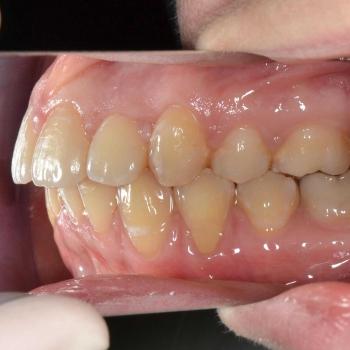

A kezelés befejeztével minden felmerülő problémát és eltérést sikerült megoldanunk, így egy funkcionálisan és esztétikailag is szép eredményt kaptunk.

A kezelés időtartama: 2 év